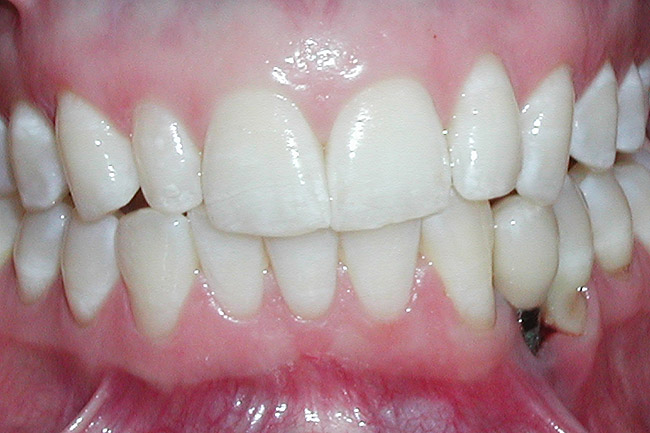

A 28-year-old Caucasian female presented to the periodontist with a complaint of a mobile implant in the site of tooth No. 22 (Figure 2 and Figure 3). The patient had a congenitally missing tooth No. 23. No. 22 had erupted into site No. 23, leaving a vacancy at site No. 22, and was the reason for the original implant at site No. 22.

Figure 2  A preoperative retracted anterior view of the failing implant in the site of tooth No. 22.

Figure 2